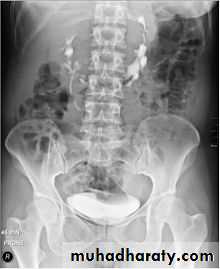

Ectopia vesica :

bladder located at low position & plain x-ray shows separation of symphysis pubis .